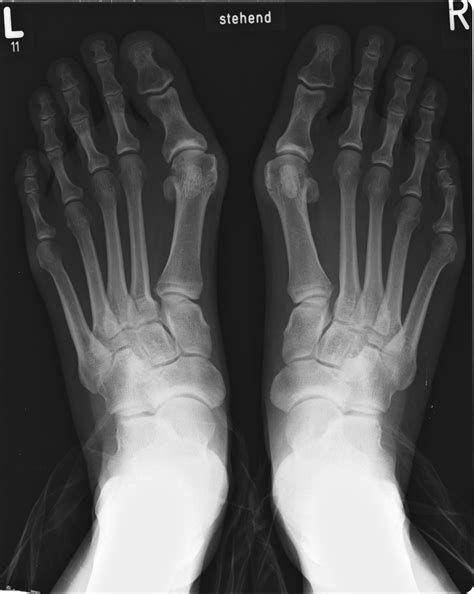

What Does Bunionette Surgery Entail? | Northwest Surgery Center